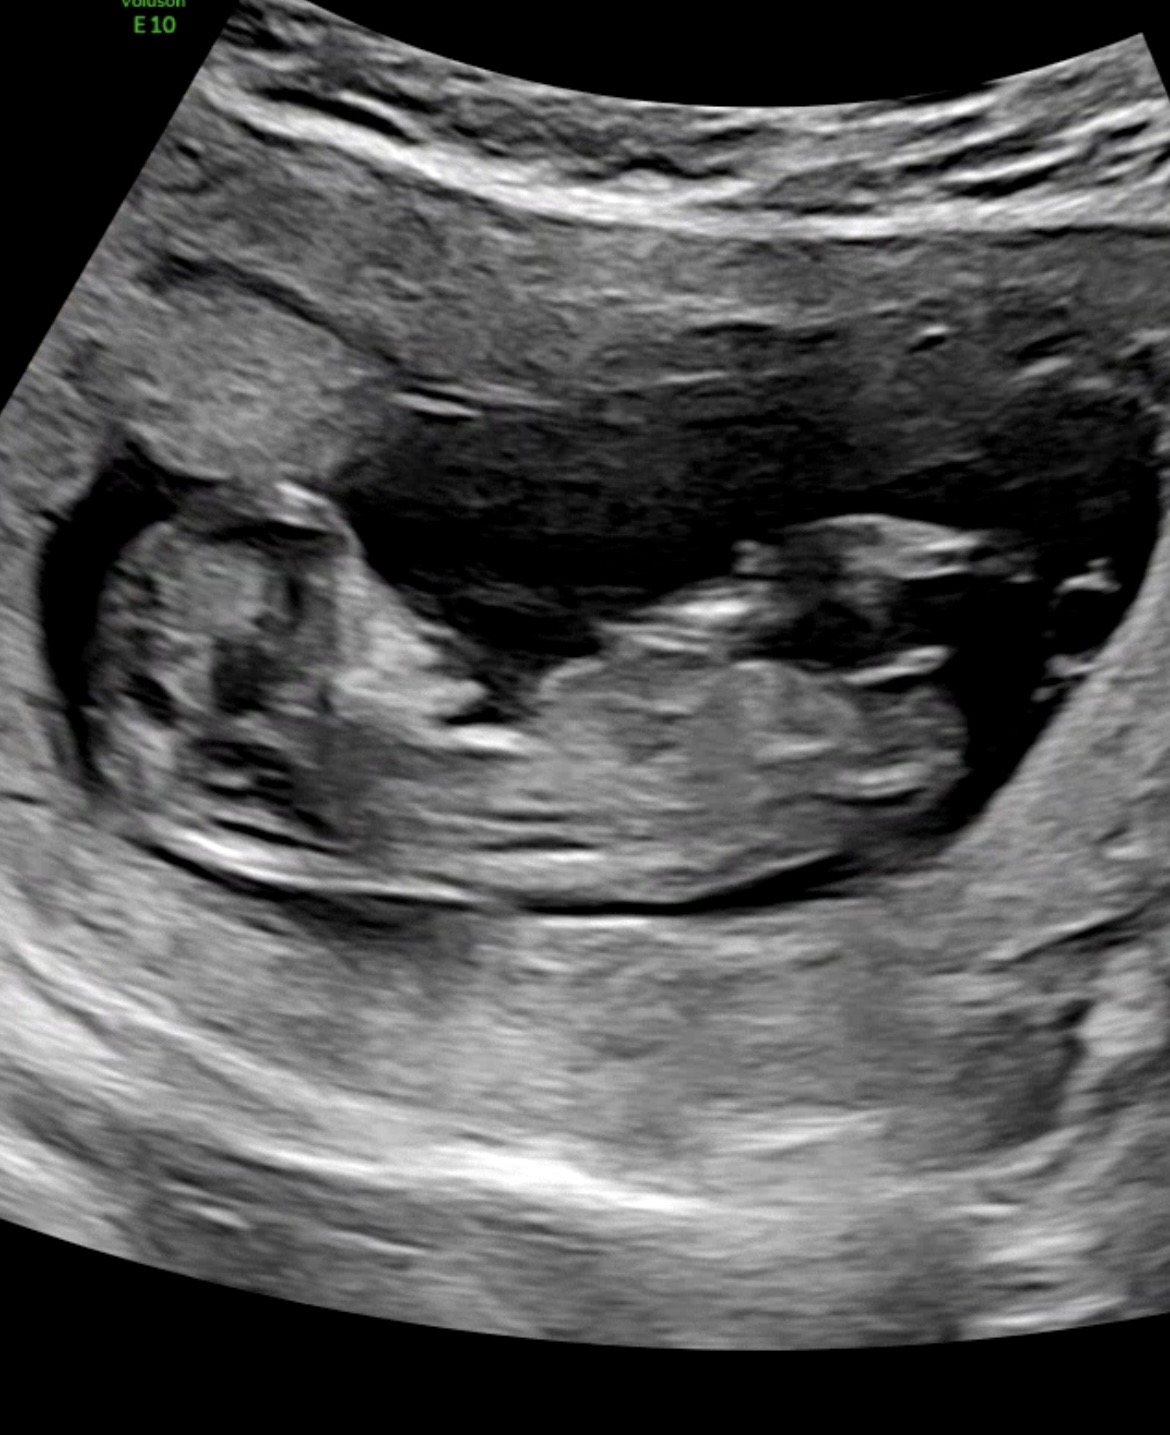

11주 6일

11주 6일이라 ㅠㅠ.. 보시기에 힘드실것 같긴한데 그래도 부탁드려요!